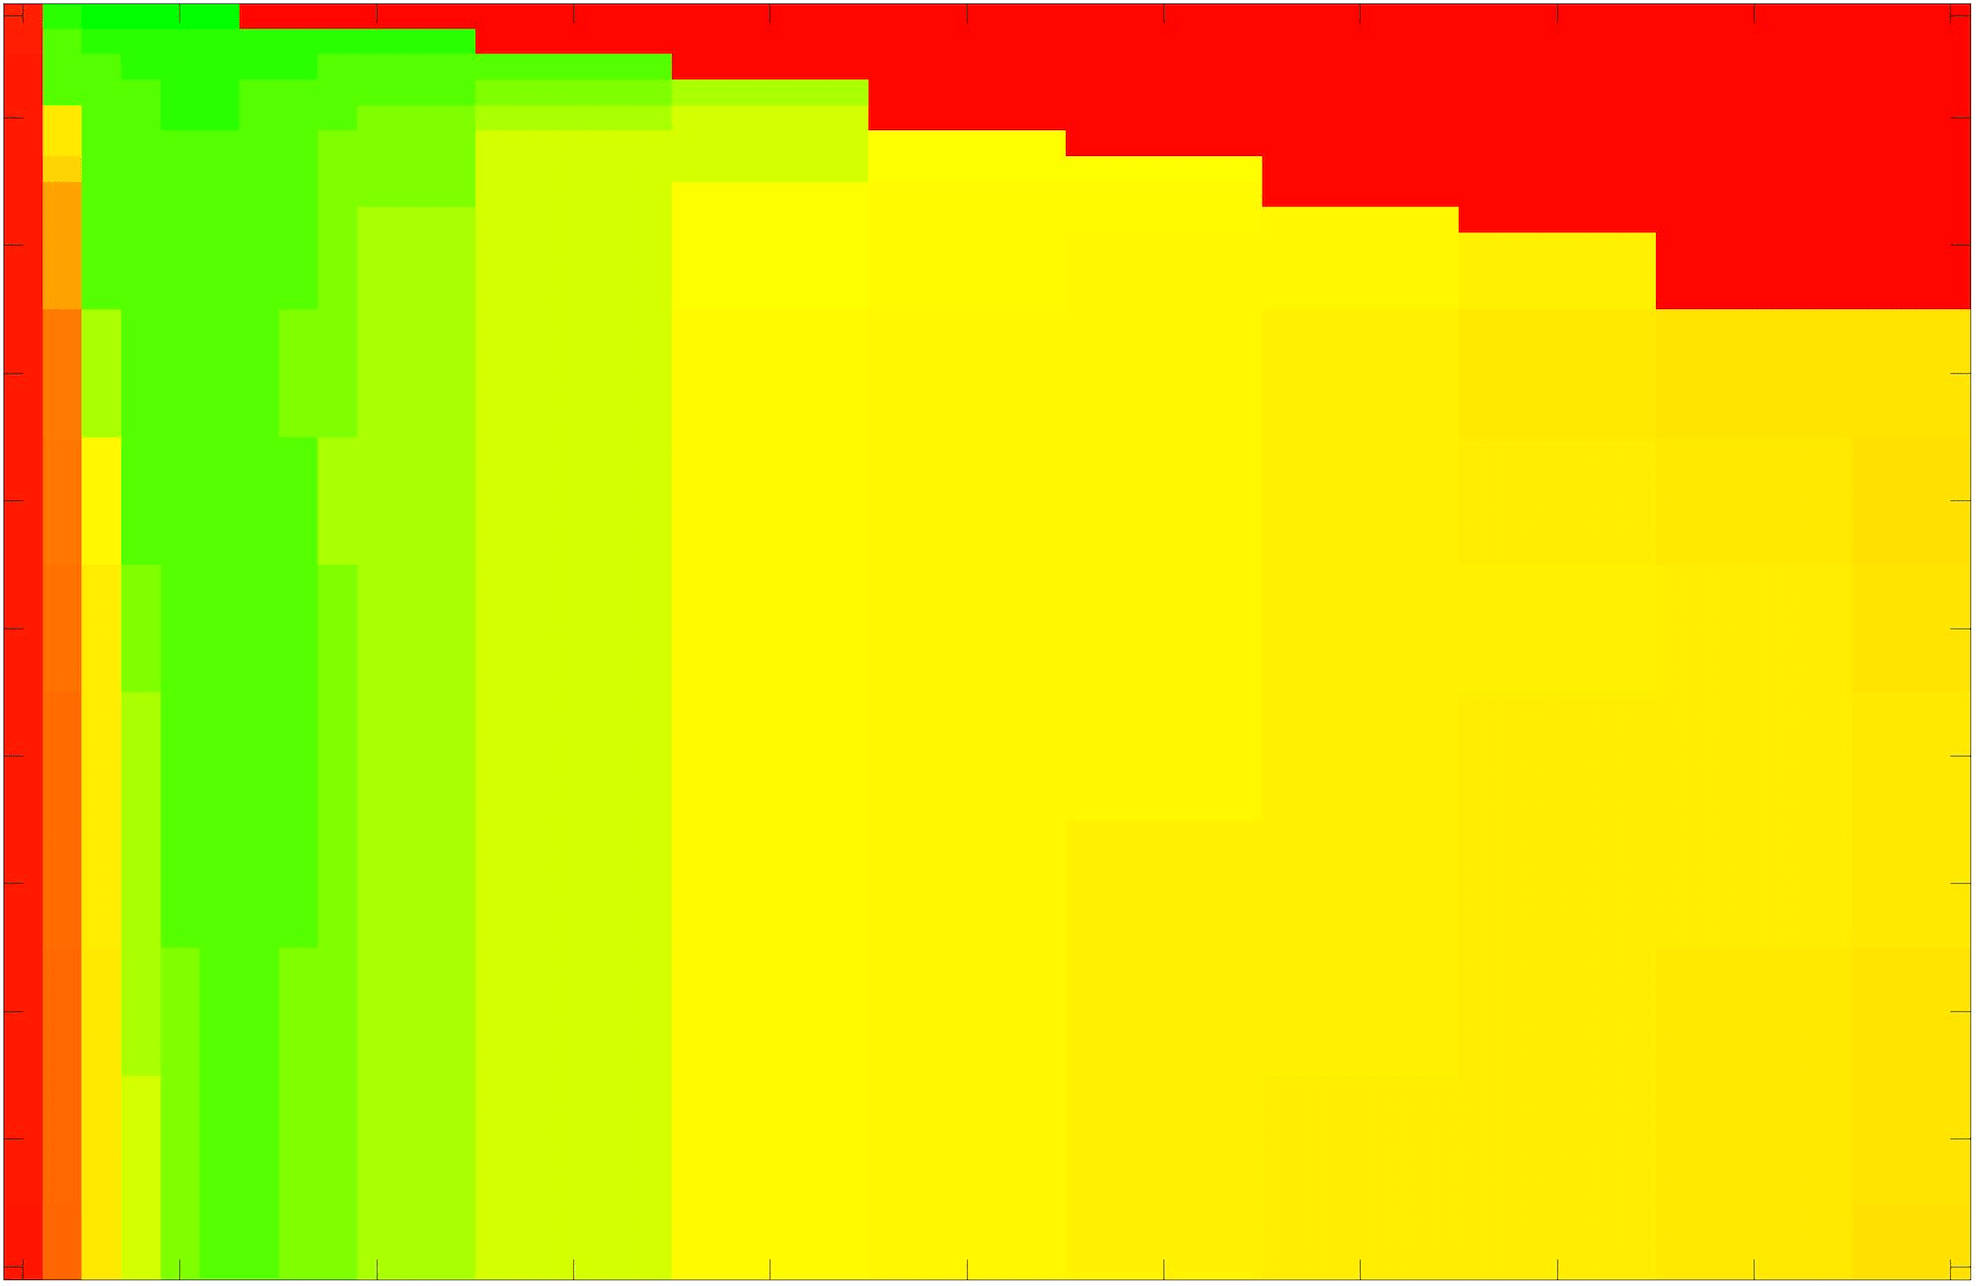

where refers to the number of points in the enclosed region. This takes values in the range , with higher TC values indicating a more accurate segmentation. In the following we will represent accuracy visually from red () to green (), with the intermediate scaling of colours used shown in Fig. 8. This will be particularly relevant in §7.2.

The TC values for the parameter sets are presented as heatmaps in Figs. 11–13. A heatmap is a convenient way to display accuracy results for hundreds of tests concisely. In Fig. 9 we give an example heatmap with the same axes used for those in Figs. 11–13. For each of the combinations of parameter values we give the TC value of the segmentation result and represent it by the appropriate colour. The corresponding colour scale is shown in Fig. 8. Qualitatively, the more green areas of the heatmap the more accurate the model is for a wider set of parameters. Example results for Test Image 5 when varying (with ) for the proposed model are given in Fig. 10. Here it can be seen what each accuracy result corresponds to visually.

Note. The axes have been removed from the heatmaps in Figs. 11–13 for presentational clarity. However, to be explicit, the axes used in all heatmaps are the same as those in Fig. 9.

Synthetic Images. These results are presented in Fig. 11. For Test Images 1–2 we see poor parameter robustness from all competing models, except for GAV which performs reasonably well. However, the proposed model has minimal parameter sensitivity for these images, with good results achieved for almost every combination of values tested. For Test Image 3 all models have a reasonable parameter range (except for RSF), however the proposed model gives better quality results for a wider parameter range. The other models achieve reasonable results here as the foreground intensity of the ground truth is greater than the background , whereas for Test Images 1–2 they are equal . These results highlight the key advantage of the proposed model.

Real Images. In Fig 12 we present results for Test Images 4–6. Here, the proposed model performs in a similar way to its competitors because these images are more typical selective segmentation problems in the sense that there is a clear distinction between the foreground and background intensities. In particular, the values in each case are: Test Image 4 , Test Image 5 , and Test Image 6 . It can be seen that the proposed model is competitive compared to previous approaches. The performance is quite poor for Test Image 5, but is arguably still the best for this challenging case. In Fig. 13 we present results for Test Images 7–9. Here the proposed model outperforms previous approaches significantly for each image. This is mainly due to the type of image considered. Specifically, the true intensities are: Test Image 7 , Test Image 8 , and Test Image 9 . The proposed model is capable of achieving results where , with other models failing completely in these cases.